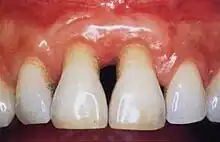

Periodontal recession on maxillary central incisors

2018 Disease Classification of Periodontal Diseases and Conditions breaks down the category of periodontitis into three forms and each of these forms are further broken down into two or more subcategories.[7]